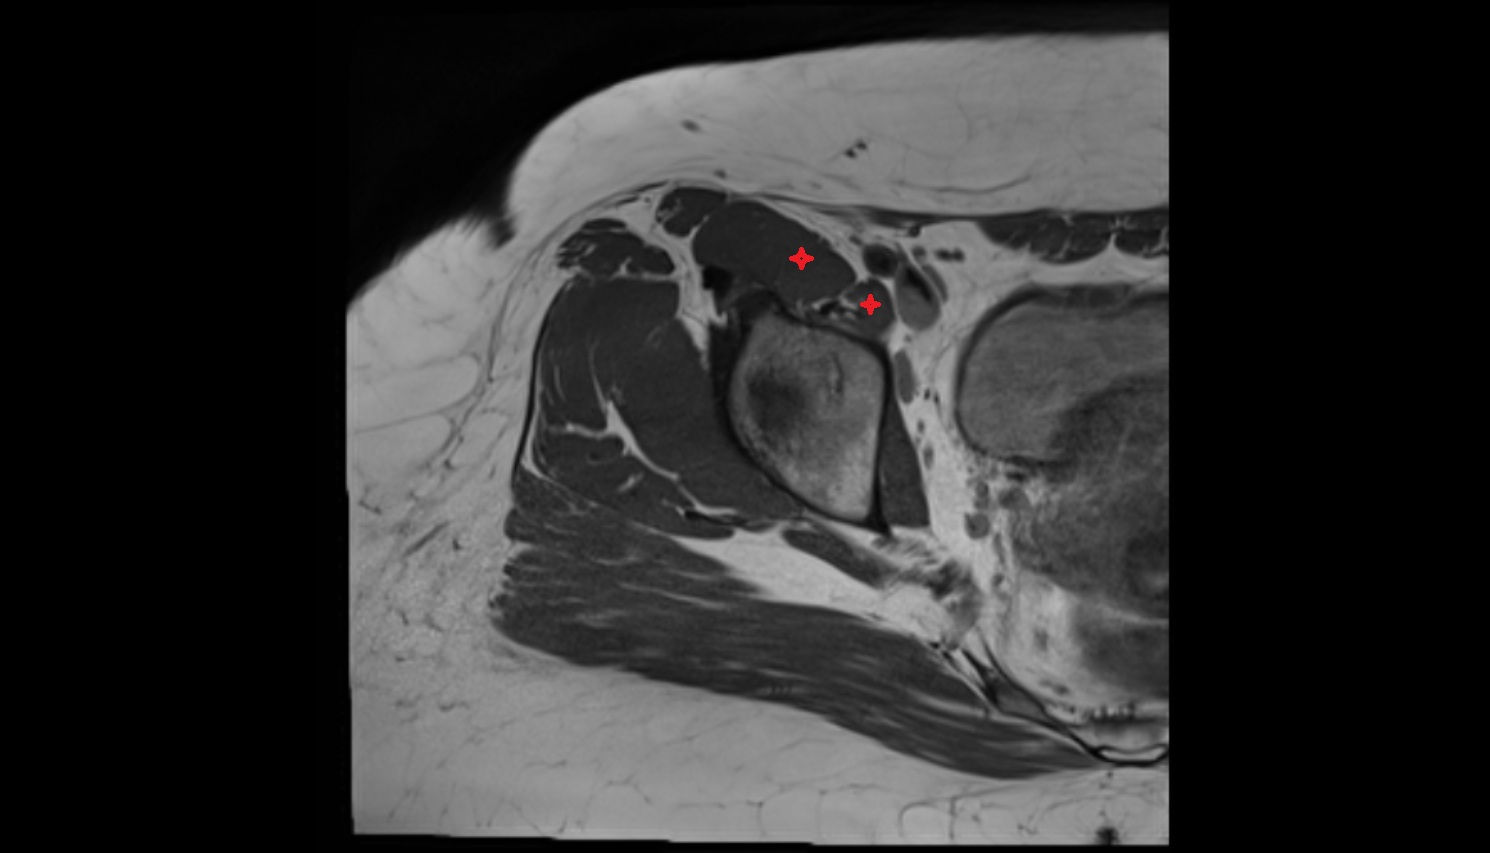

- Subacromial space